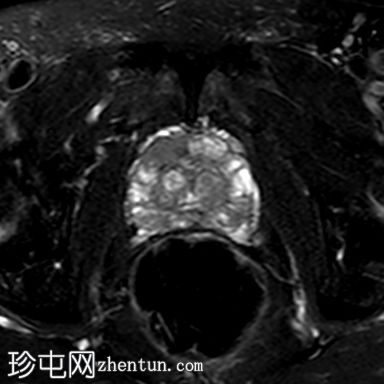

轴位T2加权像

脂肪抑制像

右侧前列腺前中带可见一边界不清的18 x 10 mm扁豆状病灶,T2加权像呈低信号,扩散受限(DWI高信号,ADC低信号),与周围实质相比早期强化,病灶位于前移行区与纤维肌性间质交界处。影像学表现符合PI-RADS 5级病灶。